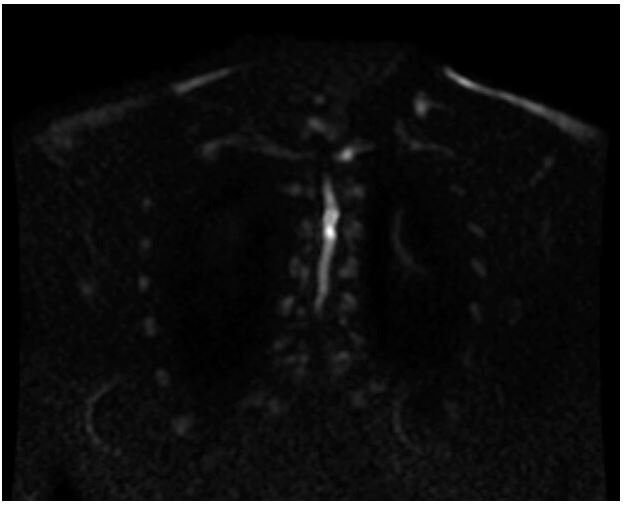

Her initial lab work was unremarkable with the exception of mild hypoglycemia of 63mg/dL, CRP was mildly elevated at 0.60mg/dL with a normal ESR. An MRI of the cervical, thoracic, and lumbar spine revealed a short segment enhancing cord abnormality which was located at the T3-T4 level involving most of the spinal cord. There was minimal disc bulging at the levels of L3-L4, L4-L5, L5-S1 without significant spinal canal stenosis or neural foraminal narrowing. No evidence of spinal cord infarction was observed (Figure 1-3). She was tested for COVID-19 given neurologic manifestations of COVID-19 which was positive. She was admitted to the hospital for workup and management of her symptoms under the Department of Internal Medicine with Neurology consultation.

Figure 1: Initial MRI thoracic spine, DWI Image, showing enhancing cord abnormality at T3-T4 level suggesting possible nonspecific transverse myelitis.